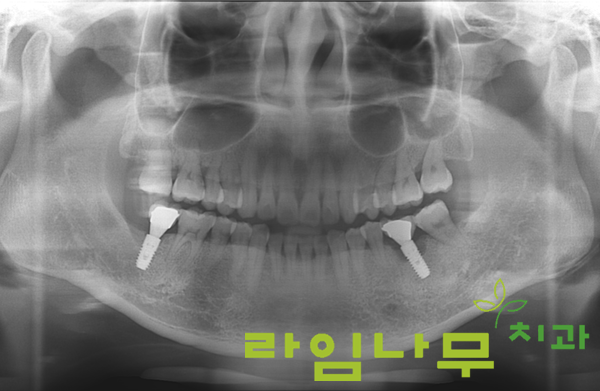

명동치과 라임나무치과의 또 다른 임플란트재수술 증례인데요,

엑스레이 상으로 왼쪽 아래 어금니에 나사 모양의 임플란트가 식립된 것이 보이는데, 그 주변부로 하얗게 차있어야 할 잇몸 뼈가 까맣게 파여있는 것이 보이시죠?

뼈 손실이 많이 이루어졌기 때문에 임플란트를 제거하고 뼈이식을 진행하여 뼈가 충분히 단단하게 차올랐을 때 임플란트를 재식립하게 됩니다.

수개월 후 임플란트 주변부 치조골의 상태를 확인하기 위해 엑스레이를 촬영했습니다.

라임나무치과의 풍부한 노하우로 진행된 수술과 환자분의 치료, 관리 협조로 임플란트 재수술에 성공하였음이 확인되었는데요!

잇몸뼈가 녹아 까맣게 보이던 곳의 뼈가 다른 곳과 동일하게 다시 하얗게 잘 차올라 있는 것이 보이실 거예요.